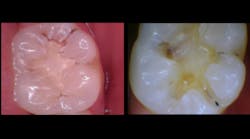

In this case, the Canary reading on tooth No. 3 was 32 from the distal-interproximal (figure 2). The caries had just begun to extend into the dentin, yet we discovered it early enough to keep the restoration conservative and preserve a significant amount of healthy enamel. We have recommended restoring other interproximal areas.

Figure 2: The Canary reading on tooth No. 3 was 32 from the distal-interproximal. The caries had just begun to extend into the dentin.